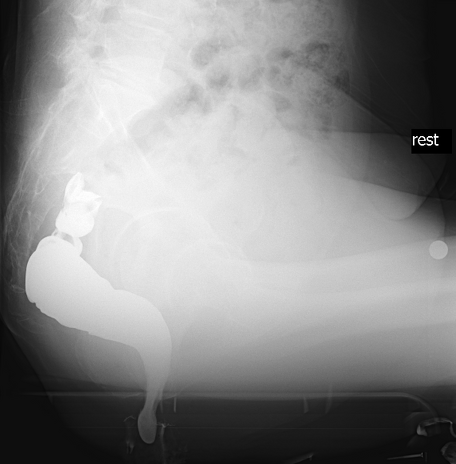

排便造影検査(ディフェコグラフィー)

お尻から擬似便(バリウムと小麦粉で作った物)を注入し、擬似便を排出する時の直腸肛門の動きをX線(レントゲン)で確認します。

主に排便時の直腸肛門の動きや形態の変化、直腸瘤の有無を評価します。